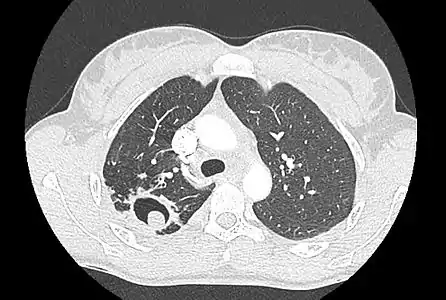

Sur la radiographie pulmonaire, un aspergillome simple apparaît comme un nodule dense, le plus souvent entouré d'un croissant aérique[11]. La radiographie seule ne suffit pas au diagnostic ; un scanner est recommandé[29]. Sur le scanner thoracique, le centre de la cavité est occupé par l'aspergillome[58]. La pseudo-tumeur bouge dans la cavité lorsque le patient change de position (signe de Monod)[58]. Dans l'aspergillome simple, il n'y a pas d'évolution entre les examens et la paroi de la cavité est le plus souvent fine[13]. Un aspergillome complexe[13] présente en revanche l'aspect d'une cavité (ou plusieurs) à parois épaisses, comportant en son centre une truffe aspergillaire. Il existe parfois un début de fibrose pulmonaire[59]. La plèvre adjacente a également un aspect fibrosé, et l'évolution radiologique est lente, mais toujours vers l'aggravation[13]. Un halo en verre dépoli peut également entourer les lésions[45].

Aspect scannographique typique d'un aspergillome développé dans une caverne tuberculeuse.

Le changement de position modifie la position du grelot aspergillaire dans la cavité (signe de Monod).